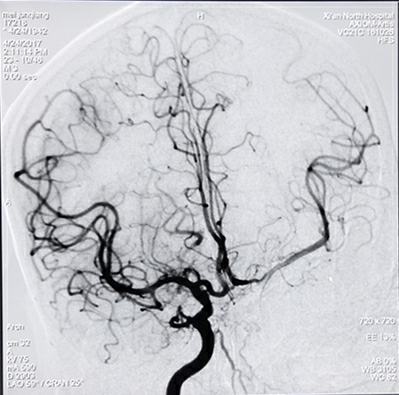

病例一:急性脑梗死取栓治疗

实施取栓治疗后完全恢复(下图)